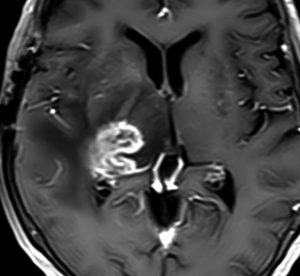

bizarre! 異様な細胞が混在しています。核多型が目立ち,多核巨細胞も混じる典型的な膠芽腫の像です。下の左の画像は血管内皮の肥厚 endovascular proliferationがあり,下の右のKi-67染色では核濃染像が多く核分裂能が高いことを示します。しかし,——

左のGFAP染色では一部の細胞が染色されません,右のHE染色では豊富な血管増殖の間に空砲 perinuclear halo を有した細胞増殖が見られます。さらに,–

腫瘍の部分像として明らかに乏突起膠腫が混在しています。また,どの部分をみても壊死 necrosisがありませんでした。

従って,当時の診断では,この腫瘍の形態病理診断は,退形成性乏突起星細胞腫 anaplastic oligoastrocytoma WHO grade III となります。2018年時点では,もしiDH変異があったと仮定すると,secondary glioblastoma (IDH-mutated glioblastoma)とされるかもしれません。